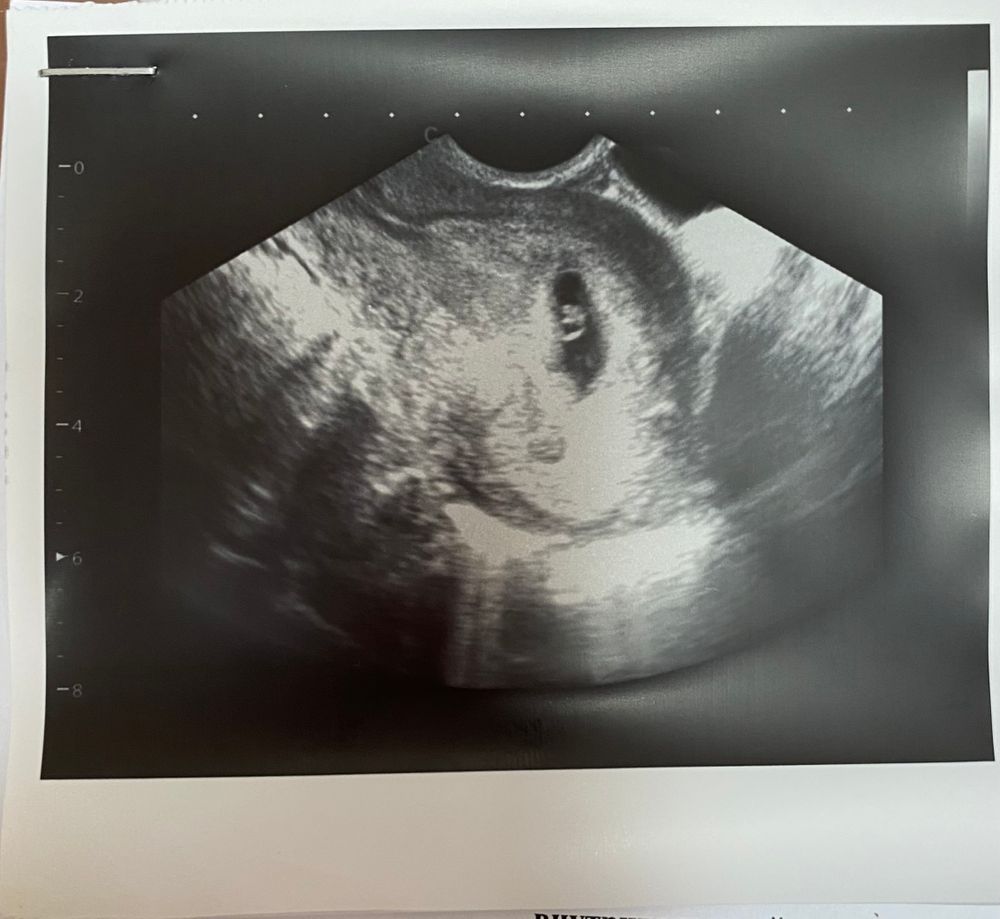

УЗИ на 6н 4д

Всем привет! Сегодня было узи, эмбриончик есть, сердечко прослушивается. Переживаю, что по неделям отстаем, хотя узистка сказала, все нормально.